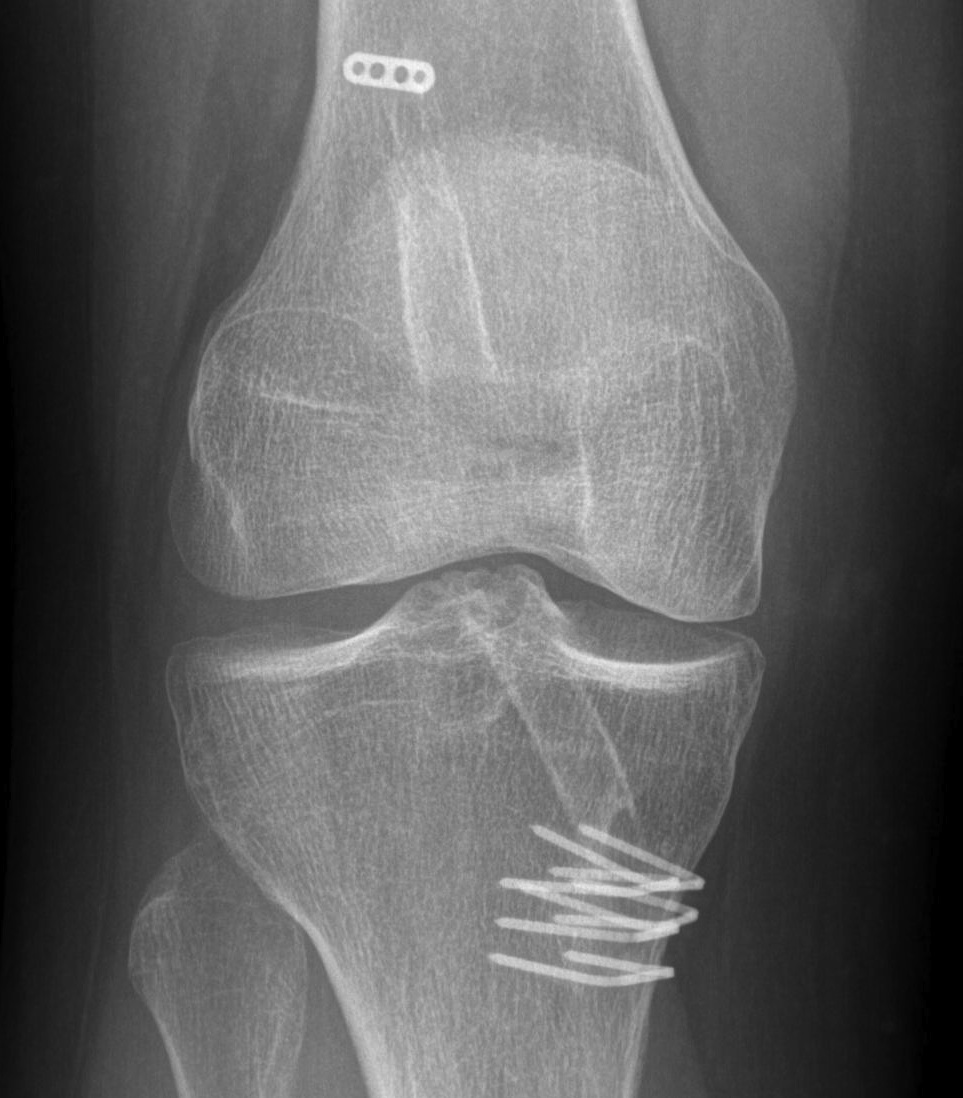

Achilles allograft used, and 12 mm x 20 mm bone plug used in femoral side. Both tunnels drilled where indicated.

Tibial screw ignored, old femoral tunnel ignored. 12 mm tunnels drilled.

Old staple had to be removed. Graft passed and fixed on femoral side with 9 x 25 mm screw.

Achilles tendon fixed on tibial side with 9 x 25 screw

Tibial bone very poor and screw little bite (advanced very easily too far into tibia, but not seen in joint).

New staple used, but had to be repositioned as cortical bone soft and fracture easily.